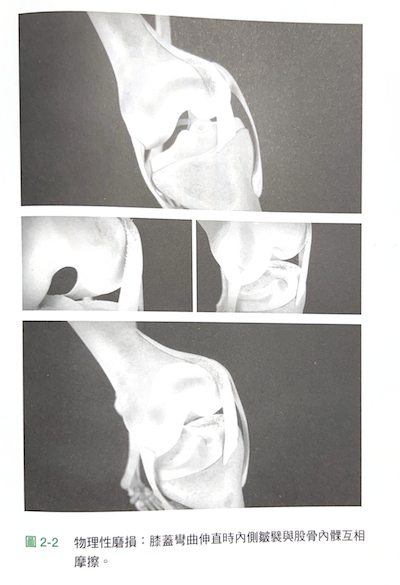

下圖摘自呂醫師著作《自己膝蓋自己救》圖 2-2:

▹ 62~63 頁:內側皺襞是在胚胎發育過程中,殘留在膝關節滑膜腔中的皺襞(圖2-1),外型像是衣服的皺褶,幾乎每個人出生時都有這個構造。我們的膝關節平均每年彎曲多達百萬次,每次膝蓋彎曲、伸直時,「內側皺襞」會與「關節股骨內髁」會互相摩擦(即「內側摩擦現象」)。年輕時,內側皺襞平滑、薄如蟬翼,經年累月摩擦、反覆發炎後,會隨著年齡的增加而漸漸失去彈性、變厚、變硬,開始磨損股骨表面的軟骨;內側皺襞本身被重複夾擊而產生的發炎現象則會釋放出有害的化學物質,使關節軟骨逐漸崩解;軟骨磨損或崩解後產生的碎片掉到關節中,產生更多不正常摩擦而導致軟骨加速破壞。

呂醫師在書中提到,許多「原發性」膝關節炎的原因不是退化,而是:內側皺襞與關節軟骨之間產生的「內側摩擦現象」引起的「內側摩擦症候群」。(62頁)書中有一段很詳細的描述: